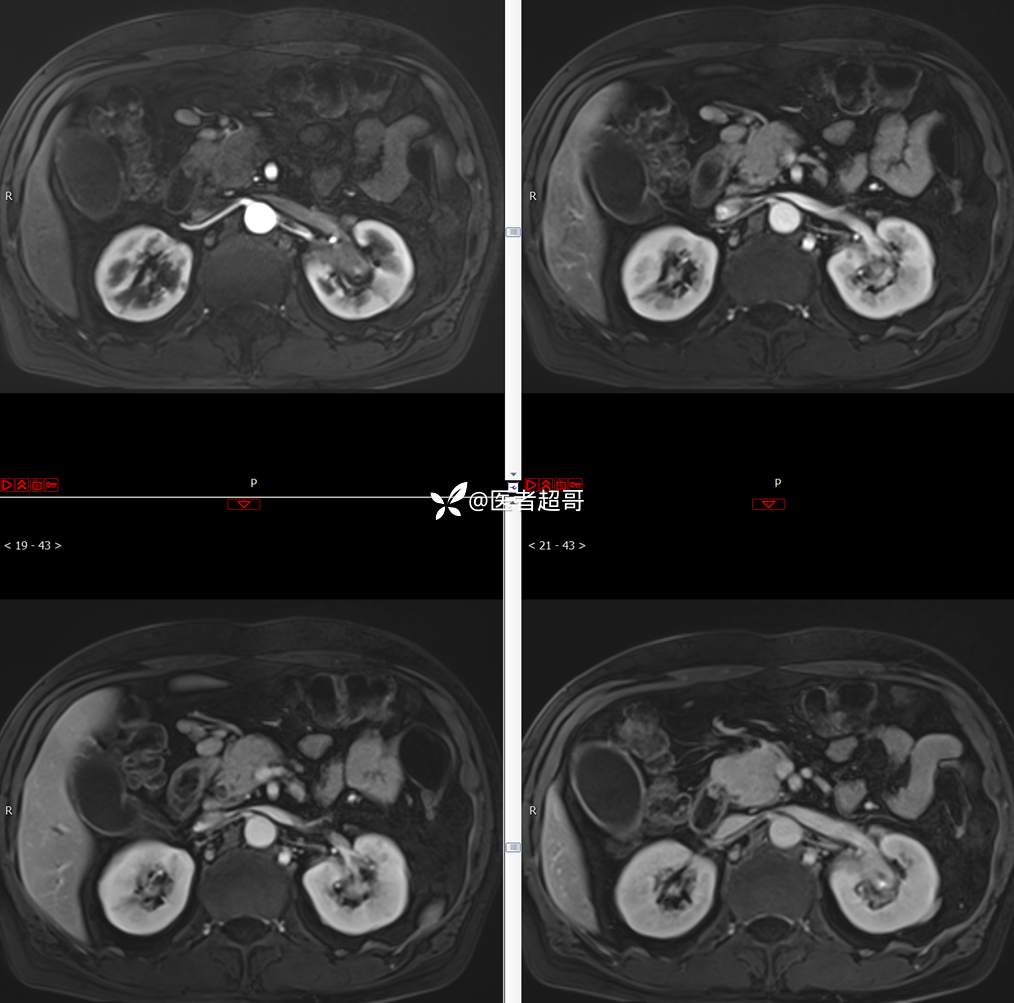

【影诊笔记772】腹痛就诊,发现肾脏病变,CT、MRI齐全,请高诊!

男,63岁 0200825 01

主 诉:间断腹痛15天

现病史:患者15天前无明显原因及诱因出现腹部疼痛不适,呈间断性钝痛,右下腹为著,无尿频、尿急、尿不尽,无发热、寒战,无腹胀。于市中心卫生院住院治疗,超声示:胰头低回声包块,胆系扩张,左肾囊肿,胆囊壁毛糙,胆囊内胆汁淤积。患者为求进一步诊治,遂以“肾盂肿瘤”收入院,患者自发病以来,神志清,精神可,饮食睡眠可,大便无明显异常,近期体重无明显增减。

既往史:既往体健